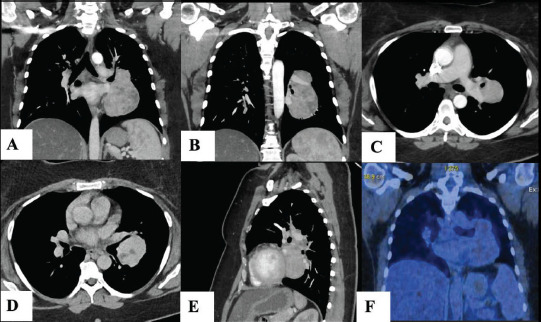

Methods: We report the case of a 42-year-old woman who underwent resection of an 11 cm intrapulmonary UCD. Additionally, we conducted a systematic review of the demographics, clinical presentation, diagnosis, and treatment approaches for intrapulmonary UCD.

Results: Our review identified 35 documented cases of intrapulmonary UCD, including our case. The average age was 34 years, with a female predominance of 57.7%. Tumor sizes ranged from 1.5 to 11 cm, with our case being the largest. Of the 24 cases with reported anamnesis, 58.3% were asymptomatic, while 41.7% had nonspecific symptoms such as cough, chest pain, or fever (as in our case). Histological analysis was available for 24 cases, with 83.3% identified as the hyaline vascular type. Biopsies through small needle aspiration or fresh-frozen samples failed in all attempts, requiring resection for diagnosis and treatment. Due to high vascularity, delicate location, and lack of diagnosis, lobectomy or pneumonectomy was performed in 45.7% of cases. Among the 11 cases with reported follow-up, no disease recurrence was observed over an average of 3 years.

Conclusion: Our systematic review highlights the rarity of UCD in the lungs. The demographics of intrapulmonary UCD align with the general disease profile. Surgical removal is crucial for both diagnosis and treatment. The significant vascularity and pulmonary location of these tumors present challenges, requiring pre-operative awareness and precautions.